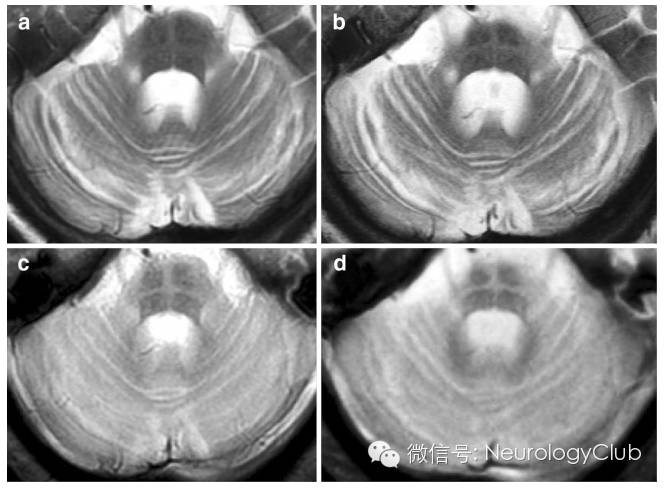

T2*WI诊断MSA的敏感度高于T2WI

近来的研究表明,梯度回波序列(T2*WI)比T2WI在发现MSA“十字征”和壳核改变上更为敏感。临床上怀疑MSA而普通MRI正常的患者,必要时可进一步行T2*WI检查。

72岁女性,诊断为MSA-C。a,c为最初的MRI;b,d为1年后复查的MRI。a-b:T2-WI;c-d:T2*WI。T2*WI相比T2WI在不同时期能更清晰的显示“十字征”